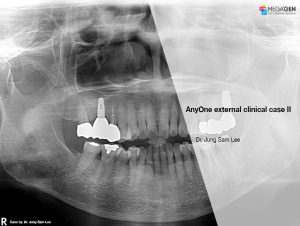

e.g. product name, treatment solution, author, clinician name